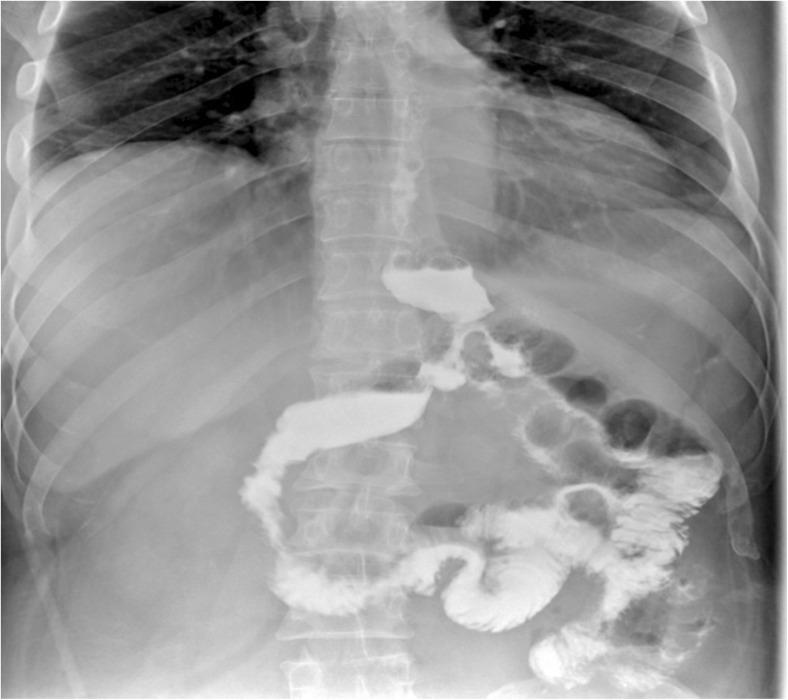

The patient presented 20 days following a laparoscopic sleeve gastrectomy in a severe septic condition and was found to have a gastric leak. During surgical repair, unlike the usual single proximal fistula findings, another opening was identified more distally. Decision was made to proceed with a double fistulo-jejunostomy. It was a feasible technique, with no intra-op complications. Post-operatively, the patient had a successful recover, with no residual leak.

患者在腹腔镜袖状胃切除术后 20 天出现严重感染,并发现有胃漏。在手术修复过程中,与通常的单一近端瘘口发现不同,在更远端发现了另一个开口。决定进行双胃瘘空肠吻合术。这是一种可行的技术,术中没有并发症。术后,患者恢复顺利,没有残余漏。